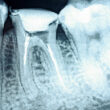

Na imagem abaixo, é fácil perceber a importância da cânula metálica da Colibri Plus

Breakable. Podemos notar a cor característica da pasta fluida na região de sulco gengival, nosso maior desafio!

Além disso, também podemos observar que as duas consistências de material estão

apropriadamente unidas, o que indica polimerização simultânea.